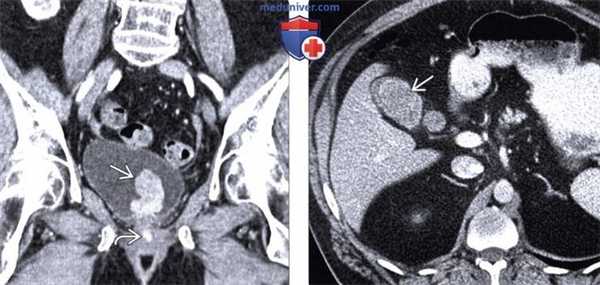

(Слева) При МРТ в аксиальной плоскости на Т1ВИ в подкожной жировой клетчатке верхних отделов спины визуализируется крупное округлое объемное образование, которое обладает изоинтенсивным сигналом по сравнению с мышцами и наличием гиперинтенсивных включений. Выявляются увеличенные подмышечные лимфатические узлы.

(Справа) При МРТ в аксиальной плоскости на Т2ВИ в режиме FS определяется доминантное объемное образование с гетерогенно гиперинтенсивным сигналом. Увеличенные подмышечные лимфатические узлы гомогенно гиперинтенсивны Пациент 18 месяцев назад обнаружил припухлость в этих областях. Четырьмя годами ранее он перенес резекцию нескольких образований на коже руки. (Слева) У этого же пациента при ПЭТ/КТ объемное образование характеризуется интенсивным уровнем накопления F-18 ФДГ. Менее выраженное накопление ФДГ регистрируется в подмышечных лимфатических узлах, что, как было показано, отражает наличие в них метастазов.

(Справа) У этого же пациента при цветовой допплерографии в продольной проекции в левой половине задней грудной стенки визуализируется объемное образование гетерогенной эхогенности. Выявляется выраженная васкуляризация этого образования. Также определяется слабовыраженная акустическая тень. (Слева) При МРТ в коронарной плоскости на Т1ВИ в костях и мягких тканях определяются множественные метастазы меланомы, характеризующиеся изоинтенсивным сигналом по сравнению с мышцами. Пациент поступил с безболевой желтухой, обусловленной наличием в поджелудочной железе метастазов. В остальном метастатическое поражение протекало бессимптомно.

(Справа) При КТ с контрастным усилением в аксиальной плоскости в мягких тканях визуализируются множественные метастазы, изоденсные или слабогиподенсные по сравнению с мышцами. Первичная меланома так и не была выявлена.

3. КТ при меланоме:

• Первичные опухоли и метастазы в мягких тканях проявляются объемными образованиями, изоденсными по сравнению с мышцами

4. МРТ при меланоме:

• Первичная опухоль обычно неразрывно связана с кожей:

о Изоинтенсивный сигнал по сравнению с мышцами на Т1 ВИ; могут выявляться гиперинтенсивные зоны вследствие парамагнитного эффекта меланина

о Гомогенный или гетерогенный сигнал различной интенсивности по сравнению с мышцами на Т2 ВИ о Интенсивное контрастирование различного характера:

- Гомогенное, гетерогенное, узловое или кольцевидное

• Метастазы в мягких тканях характеризуются сходными лучевыми признаками, как и первичная опухоль, однако во многих случаях метастазы с поверхностными отделами кожи не связаны

о Метастазы часто характеризуются наличием кровоизлияний, проявляющихся гиперинтенсивным сигналом на Т1 ВИ